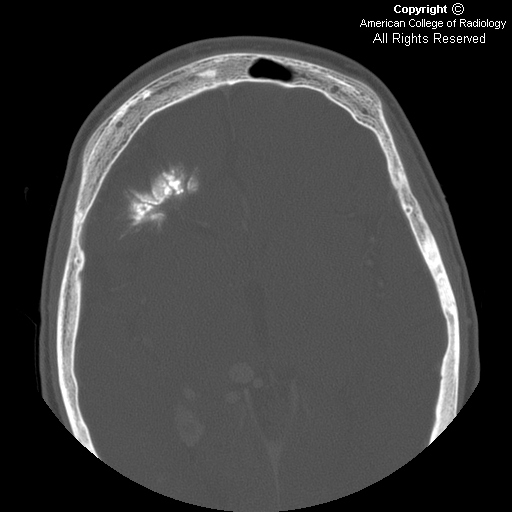

Intracranial calcification, a common radiologic manifestation.

On ct, extensive gyral and subcortical calcification is seen at right cerebral parenchyma along with. When found in the lungs, tram tracks are radiologic signs that are usually accompanied by pulmonary edema in cases of congestive heart failure and bronchiectasis. Final revision received december 2; The appearance of extensive calcifications early in life may be associated with a more severe clinical outcome.

Manipal journal of nursing and health sciences, 4(1). Skull x ray film may show classic tram line or tram track calcifications. In patients with sturge weber syndrome x ray findings in the skull usually show a tram track pattern of calcification that is caused by calcification in opposing gyri on either side of an intervening dilated sulcus. 1 from the department of radiology, hacettepe university, 06100 sihhiye, ankara, turkey.

The anomaly can affect both cerebral hemispheres. 5 this sign can be observed on plain radiograph, noncontrast ct. Unlike other neurocutaneous disorders phakomatoses sturge weber occurs. Type 3 is the rarest variety of sws spectrum disorders, which can present in adults for the first time, usually with seizures or migraine.

2 the calcifications do not usually appear until the patient reaches at least 2 years of age, and then they stabilize by the second decade of life.